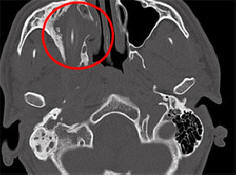

Nekatere bolezni in poškodbe so tako neopazne, da človek lahko živi z njimi več let, ne da bi nanje sumil obstoj. Kot Američan, ki si je vzel skoraj dve leti puščanje lastne možganske tekočine za izcedek iz nosu, nemški državljan uspel živeti 15 let s svinčnikom v glavi, poroča Spiegel. Kot so povedali predstavniki univerzitetne bolnišnice Aachen, Severno Porenje-Vestfalija, 24-letna afganistanska Nemka poreklo jim je priskočil na pomoč že leta 2011. Mladi oseba se je pritožila zaradi vztrajnih glavobolov, prehladov in poslabšanja vid na eno oko. Dolgo časa zdravniki niso mogli razumeti, kaj se dogaja. ni naredil računalniške tomografije. Izkazalo se je, da v moji glavi pacient je bil ves ta čas 10-centimetrski svinčnik. On je nameščen neposredno nad mladenikovo desno očesno vtičnico in postavljen nanjo tlak. Nemec, ki je želel ostati anonimen, ni znal pojasniti od kod je prišel svinčnik v glavi, a se je pozneje spomnil kako neuspešno je padel v otroštvu. Zdravniki so mu odstranili tuje telo z glave mladeniči, in kmalu si je opomogel. Šele konec maja, po skoraj enem letu po operaciji so se zdravniki odločili, da se bodo posvetili temu primeru ločena konferenca, zahvaljujoč kateri so novinarji izvedeli za to. To ni prvič, da človek že dolgo uspeva živite s tujim predmetom v telesu. Torej, leta 2007 starejša Nemka, ki trpi zaradi glavobola in krvavitev iz nosu, odstranili so svinčnik, ki je bil tam že 50 let.